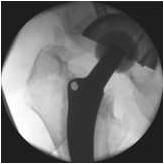

Lateral view to control plate position Lateral view to control plate position Lateral view to control plate position Lateral view to control plate position Control of rotation Control of rotation View the embedded image gallery online at: https://www.zbinetworkemea.com/fracture/index.php/treatment-example/rorabeck-i-ii-complex/item/153-plate-control#sigProIdf12d0f8d7a Plate Control Before the screws are placed a lateral view to control the plate position is performed by use of the intensifier.